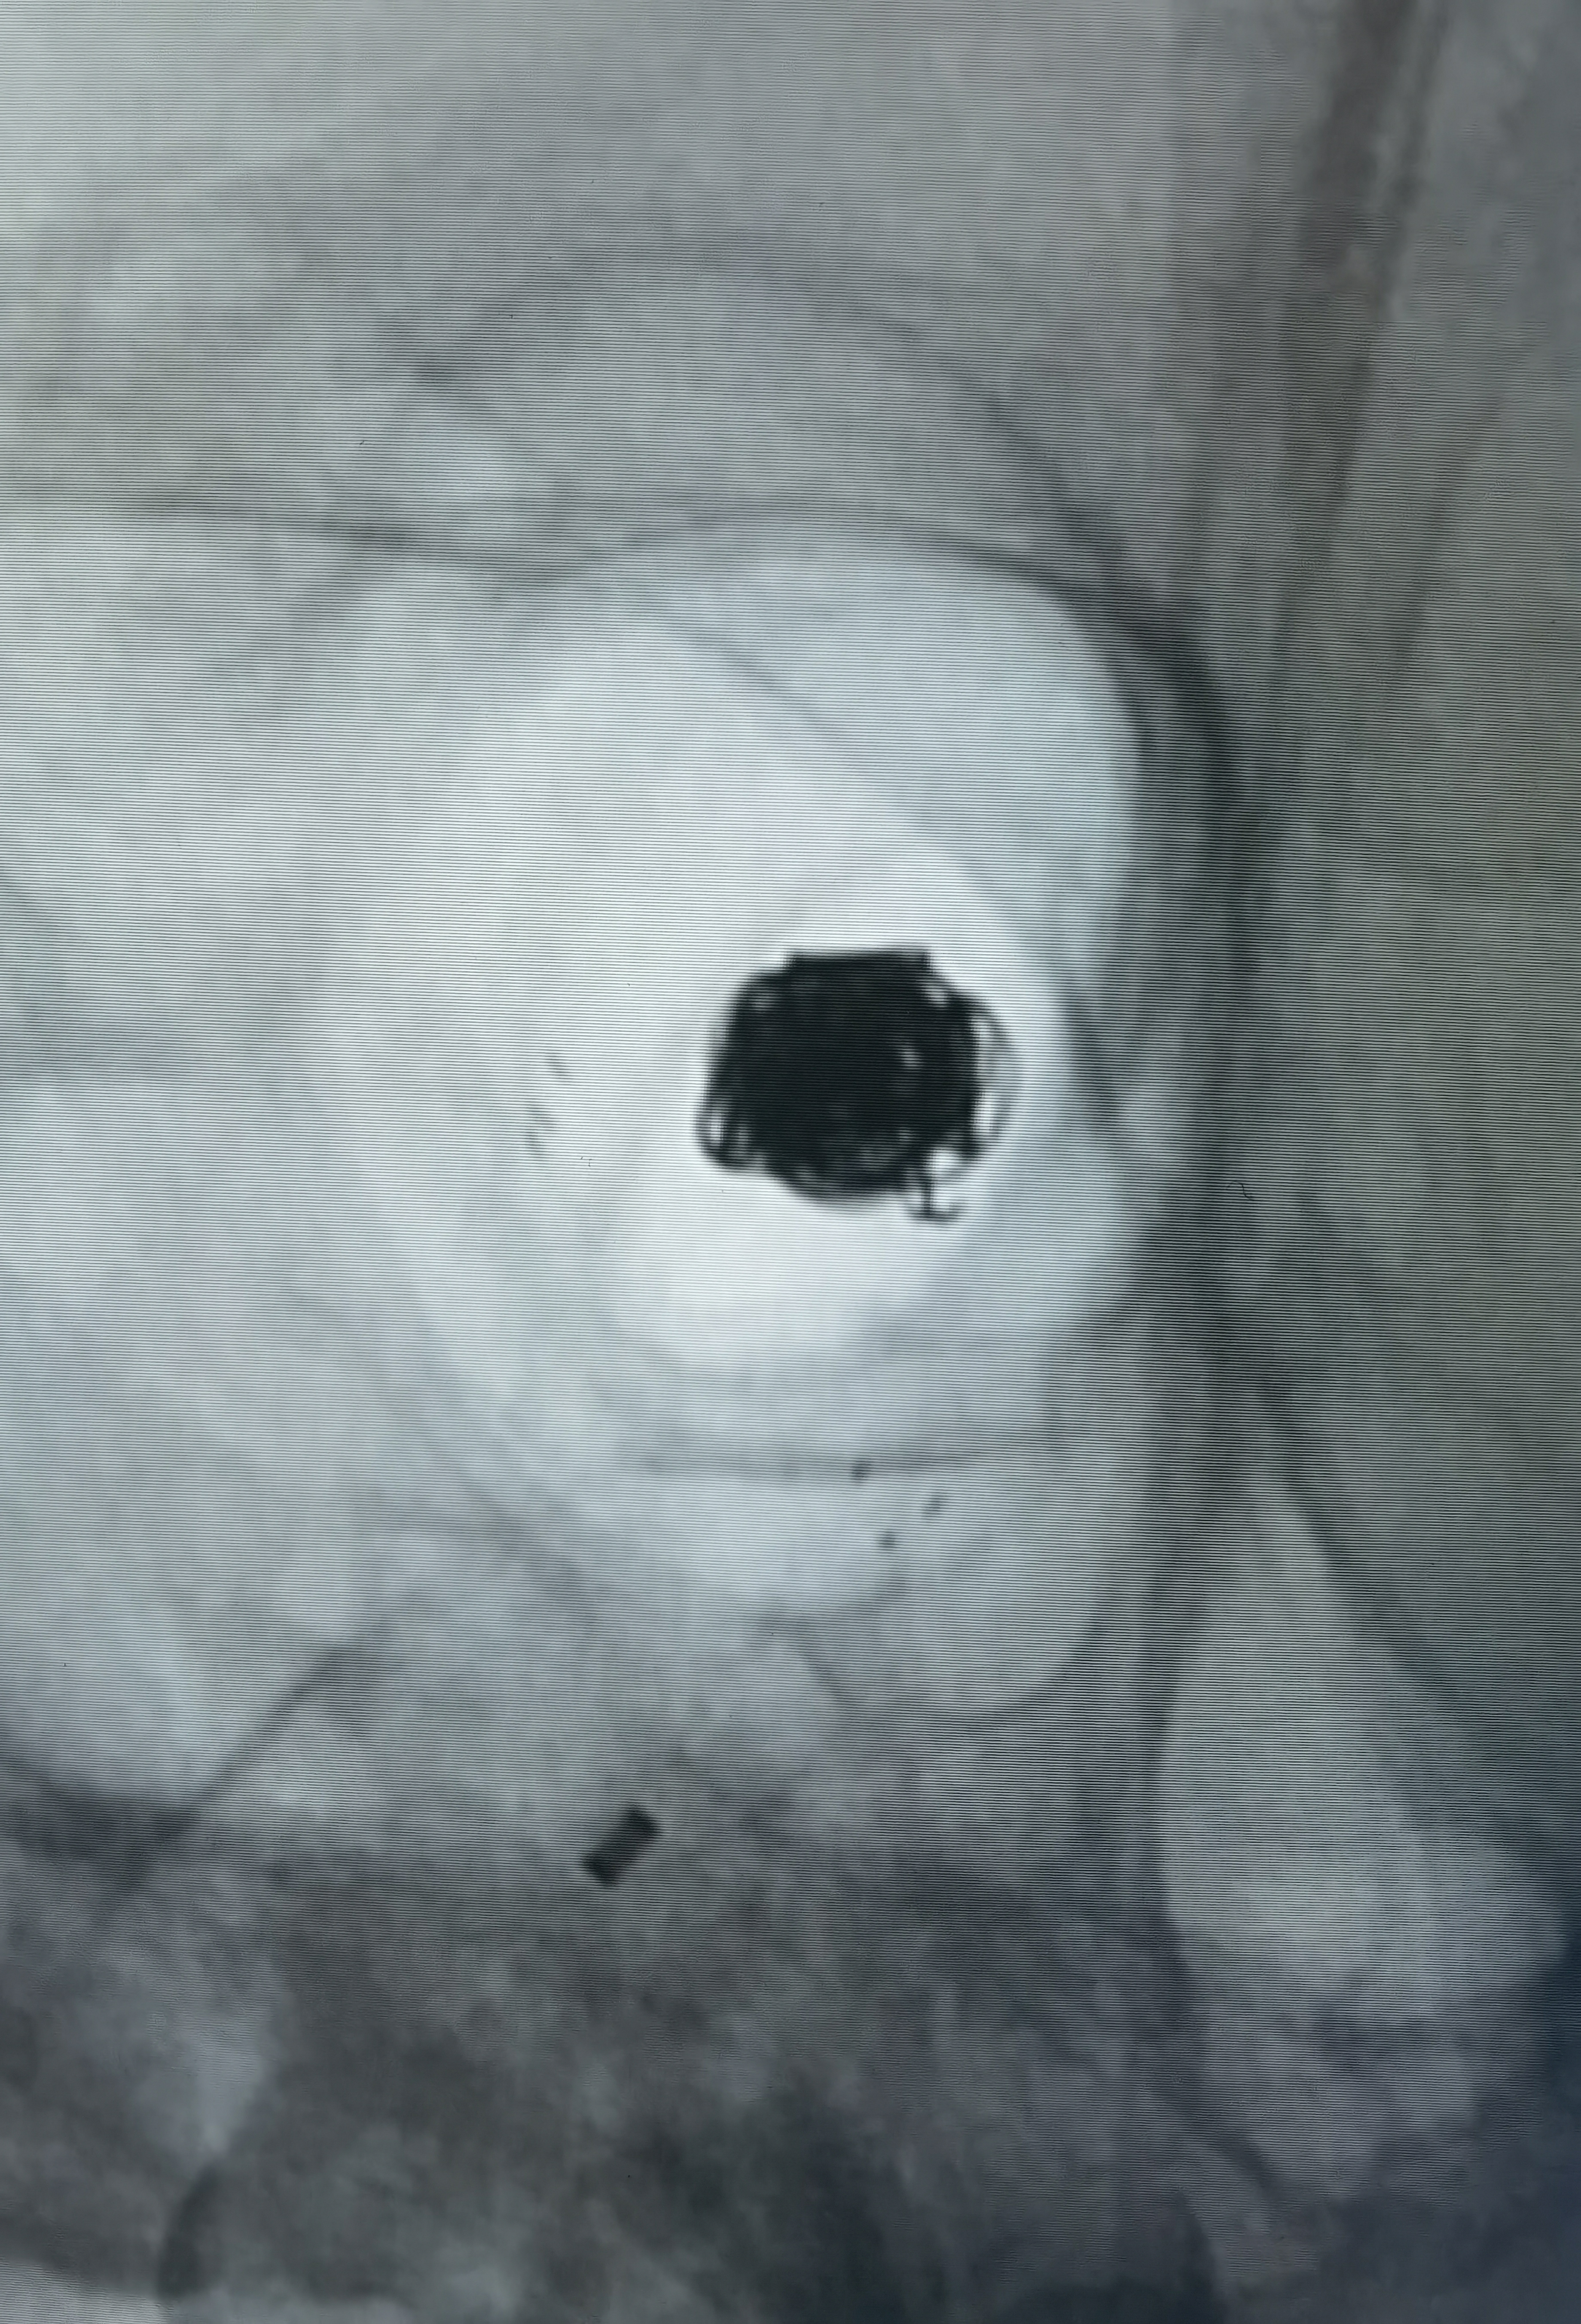

Atlas支架释放后微导管进入瘤腔,双微导管栓塞

术后造影